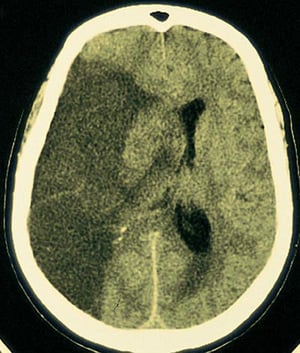

Infarkt der A. cerebri media

Im Bereich des von der rechten mittleren Hirnarterie versorgten Gehirns ist ein großer durchscheinender Infarkt zu sehen.

By permission of the publisher. From Furie K, et al: Cerebrovascular disease. In Atlas of Clinical Neurology. Edited by RN Rosenberg. Philadelphia, Current Medicine, 2002.